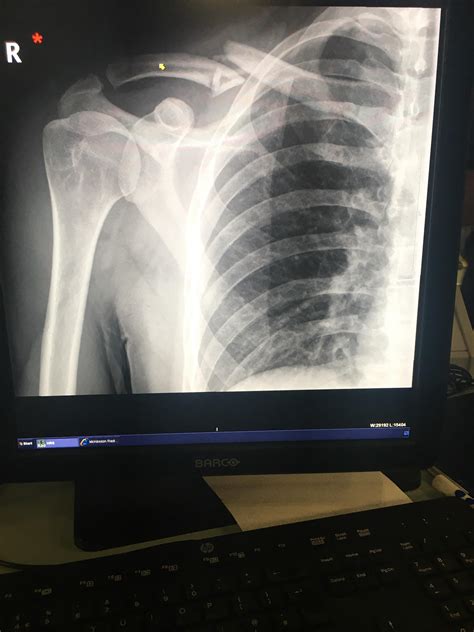

Collarbone Pain | What is Causing my Clavicle to Hurt?

Collarbone Pain | What is Causing my Clavicle to Hurt?